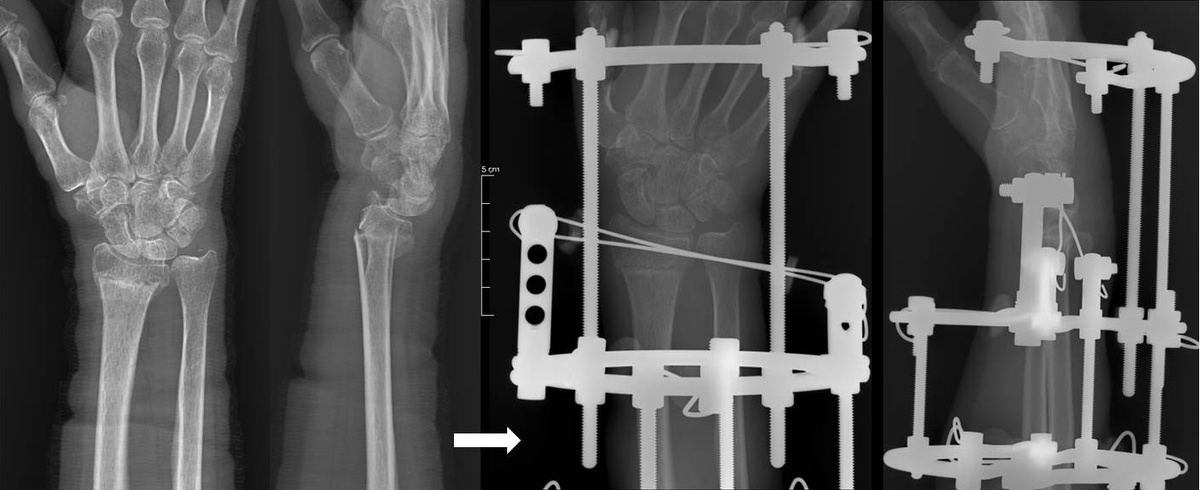

Рентгенограммы пациента 58 лет. До и во время лечения

Недавно в клинике прооперировали поскользнувшегося на льду мужчину 58 лет с закрытым консолидирующимся в порочном положении переломом дистального метафиза правой лучевой кости. Врачами отделения №1 к.м.н. Бойчуком Сергеем Петровичем и Мельниковой Людмилой Васильевной была проведена остеотомия и закрытый чрескостный остеосинтез аппаратом Илизарова – операция, требующая точности и опыта. Сейчас процесс восстановления идет хорошо, отломки в правильном положении, и мы радуемся вместе с пациентом его успехам.